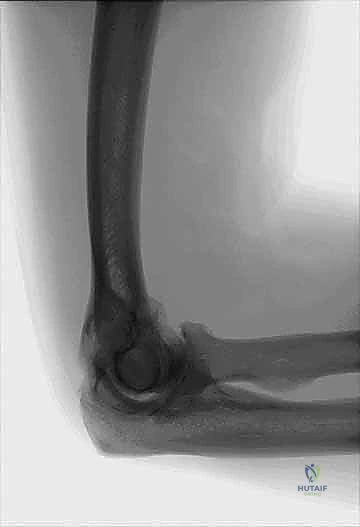

Our preoperative workup is crucial. Standard anteroposterior (AP) and lateral radiographs will reveal characteristic features: joint space narrowing, subchondral sclerosis, and prominent osteophytes in the coronoid, capitellar, and olecranon fossae.

FIG 2 A,B: Anteroposterior and lateral views of a right osteoarthritic elbow show narrowing of the joint line and subchondral sclerosis, with formation of osteophytes in the coronoid, capitellar, and olecranon fossae.

However, radiographs often don't fully delineate all osteophytes. For surgical planning, especially when considering open débridement or arthroplasty, a Computed Tomography (CT) scan is indispensable. It provides detailed structural anatomy, accurately localizing osteophytes and loose bodies, and helps us visualize the extent of articular surface involvement. Three-dimensional reconstructions from CT data are particularly valuable for planning osteophyte removal.

FIG 2 C: Computed tomography of the elbow demonstrating marginal osteophytes on the ulna and olecranon fossa.